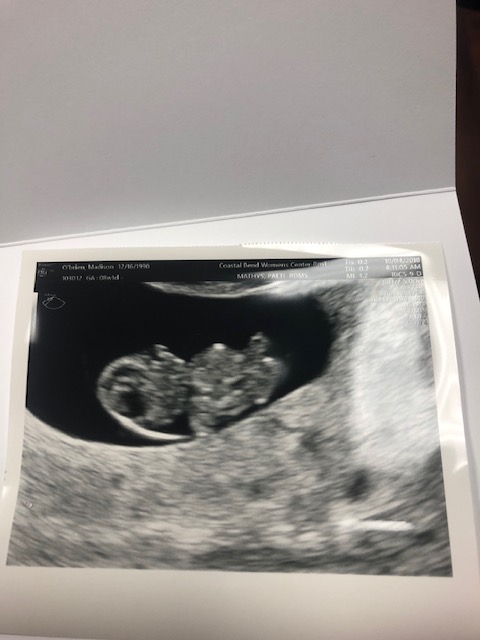

9 weeks: At 9 weeks were were able to go to our OBGYN in Corpus and have another ultrasound. Its amazing how much the baby grows in just a few short weeks. I heard on a TED talk the other day that if the baby grew at this rate the whole pregnancy it would weigh one ton. Yikes! It looked like a gummy bear. At this point I am still on my daily progesterone injections and the lumps and bruises have only gotten worse. I only have 6 more days left and most of them fall where I have to give them to myself. URGG! Needless to say I am so ready to be done shooting up in public restrooms or being not being able to walk afterwards because my ass hurts too much to move. In addition, to the injections I am in full fledged morning sickness mode. All I want is the blandest food possible; I think I am surviving on saltines, apples, and popcorn (the only things I haven’t thrown up yet).